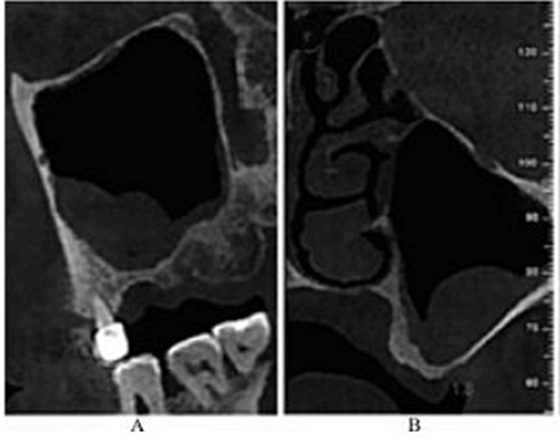

CBCT示:左侧鼻甲水肿,左侧上颌窦内可见黏膜呈半圆形隆起,密度均匀升高,未见钙化及明显骨质破坏;26牙剩余牙槽突高度(residual bone height,RBH)1.8mm,27牙RBH4.2mm,28牙RBH11mm,上颌窦颊侧骨壁厚度约1mm(图1)。

图1 术前CBCT

注:A,矢状面;B,26颊舌向切面;C,27颊舌向切面;D,28颊舌向切面。